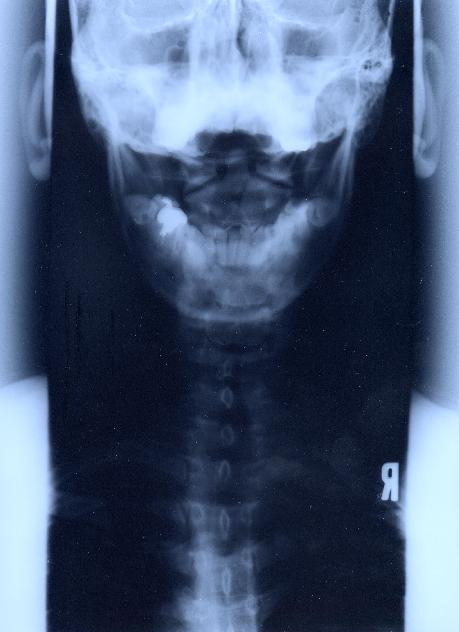

‚VD”wœ@@Šg‘ε